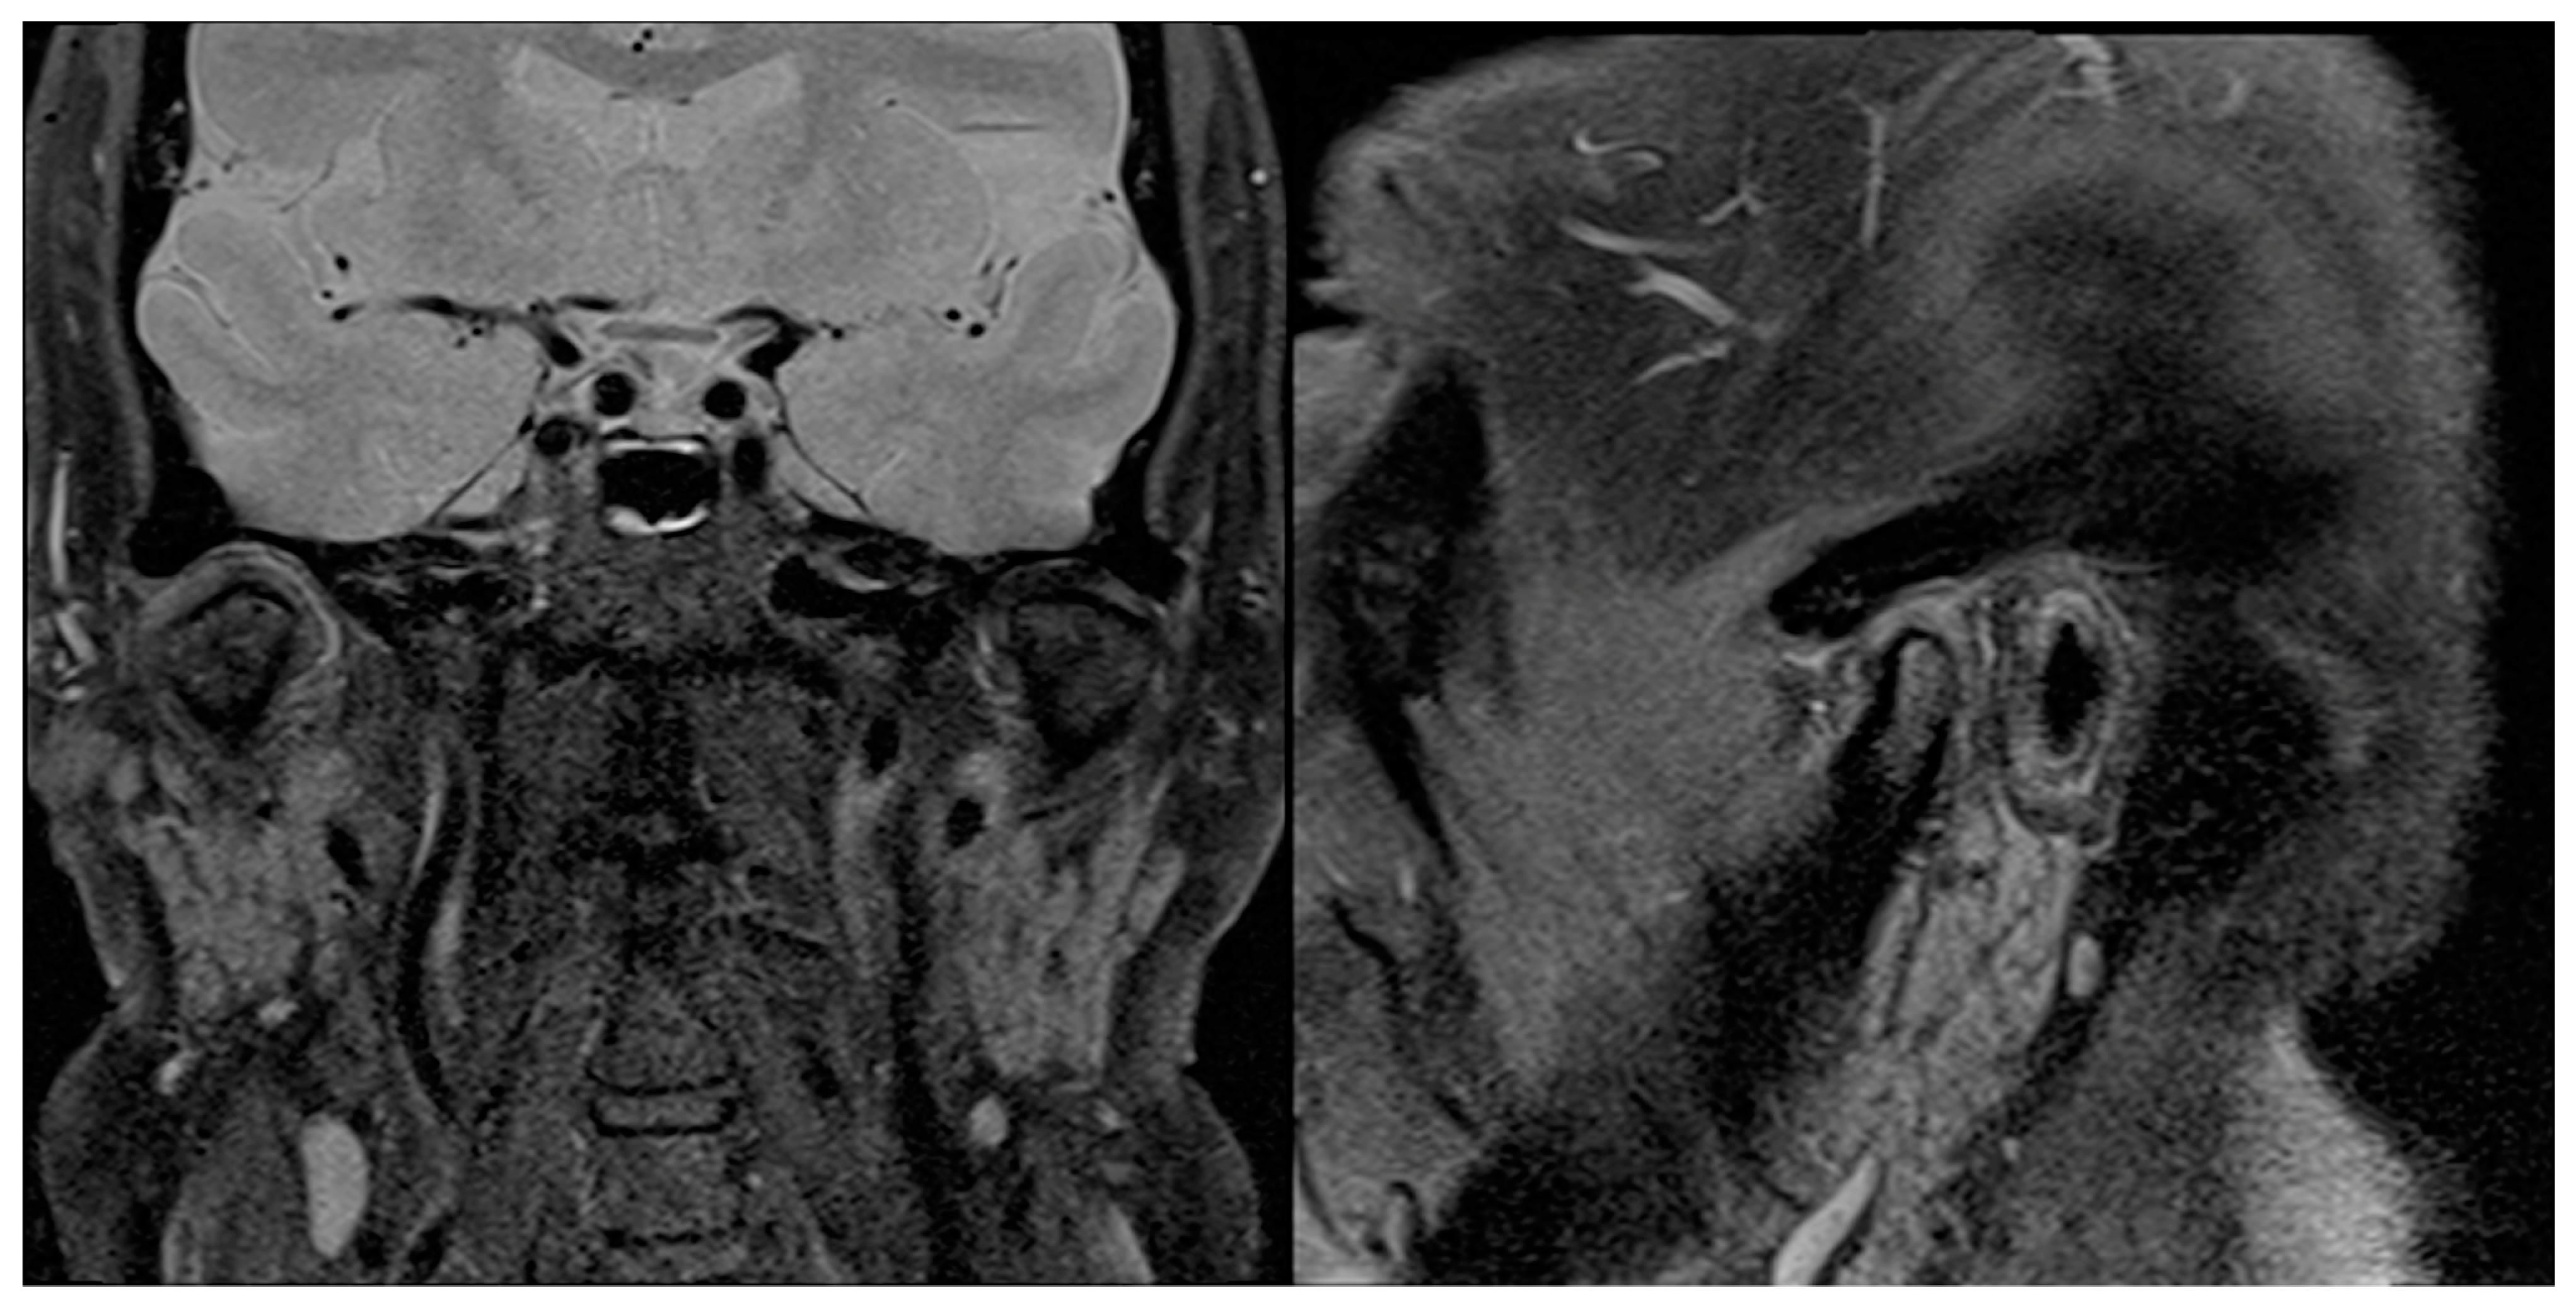

Figure 10.

The 6-month postoperative sagittal and coronal MRI scans showing no signs of relapse on the right TMJ.